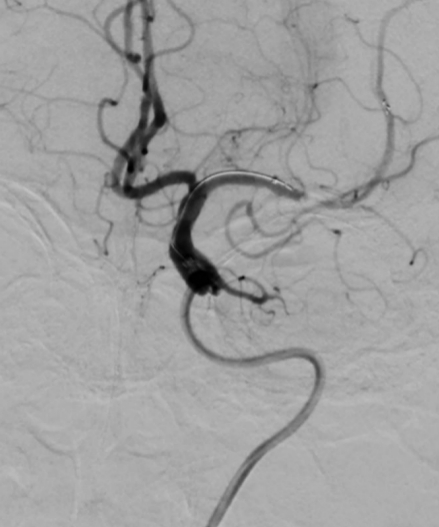

脑血管造影是目前脑血管检查的金标准,是通过动脉插管,使用造影剂显影完成脑血管检查的一种微创方法。其特点:简单、方便、安全、准确、创伤小。我院从2009年开始开展脑血管造影检查,目前开展经桡动脉、股动脉两种路径完成脑血管造影及治疗,桡动脉路径大大减轻患者的痛苦。目前开展的治疗手术:颅内外血管球囊扩张成形术、支架置入术、动脉瘤栓塞术、急症溶栓、取栓术,对于出血性脑血管病患者开展了微创血肿清除术。每年造影检查量约500例左右,治疗量约100例左右。介入技术水平走在了全市前列,取得了广大患者的好评。

图片1.jpg  图片2.jpg

经股动脉入路造影                                                               经桡动脉入路造影